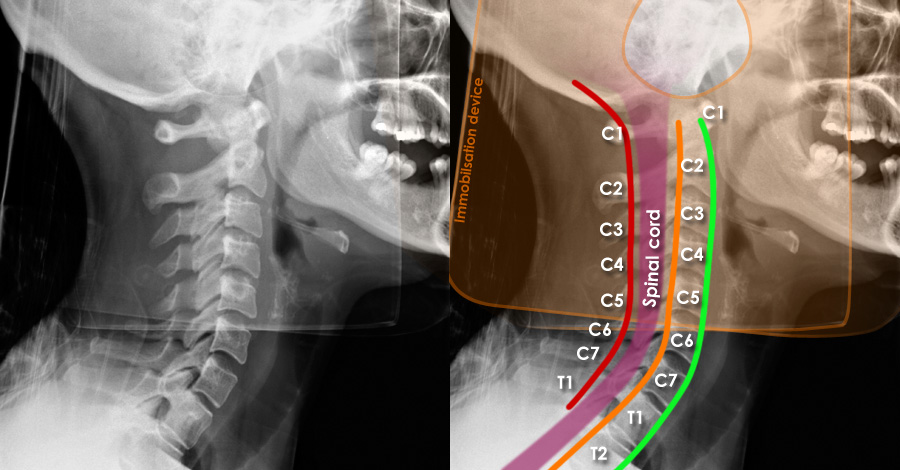

Doctors performed detailed imaging of the cervical spine and found a rare type of injury affecting two vertebrae. This kind of injury does not fit neatly into common medical classification systems, making it a unique case for medical professionals and researchers to study.

Doctors noted that this type of injury pattern is extremely uncommon. It highlighted how even a single falling object can cause serious harm and how important it is for medical teams to be aware of unusual injury presentations that may not match typical guidelines.

The incident also pointed to the need for ongoing review and improvement of classification systems used to understand and diagnose spinal injuries, ensuring that rare cases are better recognized in the future.

- Use comprehensive imaging to ensure an accurate diagnosis.